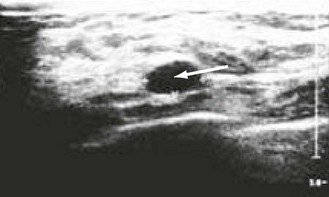

Abnormal findings: Sebaceous cysts are common in the scrotal skin. If you can get above a scrotal swelling, it is a true scrotal swelling. If not, it may be a varicocoele or inguinal hernia which has descended into the scrotum. A varicocoele feels like a ‘bag of worms’ in the cord and should disappear when the patient lies down. If it does not, then consider a retroperitoneal mass compressing the testicular veins. A bulky or painful mass in the scrotum when you cannot palpate the testis needs an ultrasound scan to clarify the nature of the intrascrotal structures.